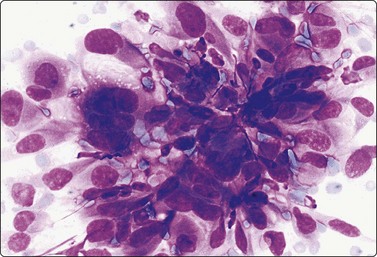

A 60-year-old woman with a history of right mastectomy for cancer 4 years previously presented with a lump in the right axilla. It was described as subcutaneous by the surgeon who performed the FNB and the clinical diagnosis was metastasis of breast cancer. Smears were highly cellular, of epithelial cells both forming cohesive aggregates and dispersed as single cells. True papillary fragments were not seen. The cells had a moderate amount of dense cytoplasm and there was relatively mild nuclear atypia (Fig. 14.10). The pattern was considered to be in keeping with metastasis of a low-grade breast carcinoma. However, the nodule was, in fact, intracutaneous and the histology was reported as syringocystadenoma papilliferum (Fig. 14.10).36

image image image

Fig. 14.10 Syringocystadenoma papilliferum

Clustered and dispersed epithelial cells; moderate amount of cytoplasm; mildly atypical nuclei; no true papillary fragments (A, MGG, HP; B, H&E, IP); (C) Corresponding tissue section (H&E, LP).